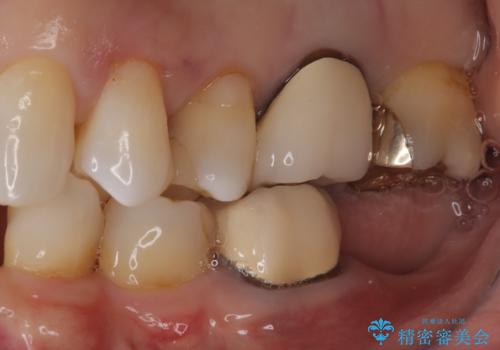

- 奥歯の被せ物が欠けたを主訴に来院された患者様です。欠けてしまった被せ物を除去後セラミックインレーで治療を行いました。

欠けた範囲が大きく被せ物を外して後、セラミックインレーで治療を行いました。欠けたままの状態を放置しているとそこに食べ物が詰まり虫歯になってしまうので早めの治療が必要です。